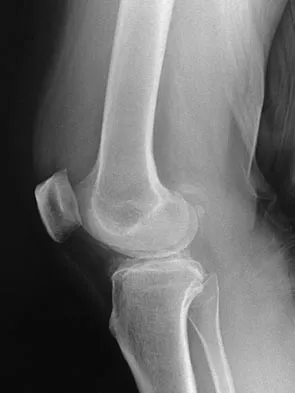

Figure 31 shows the AP and lateral radiographs of the elbow of a 56-year-old man with chronic polyarticular rheumatoid arthritis. His function continues to be limited by pain with activities of daily living. Examination shows that his total arc of motion is 110 degrees. Nonsurgical management has failed to provide relief. Treatment should now consist of

A semiconstrained prosthesis can provide excellent results in carefully selected patients. Because the radiographs show extensive joint destruction with loss of the capitellum and trochlea, a capitellocondylar total elbow (unconstrained) prosthesis is contraindicated. Elbow fusion is poorly accepted, and the radiographs show too much articular destruction for a radial head excision, synovectomy, or interposition arthroplasty to be effective. Ewald FC, Simmons ED Jr, Sullivan JA, et al: Capitellocondylar total elbow replacement in rheumatoid arthritis: Long-term results. J Bone Joint Surg Am 1993;75:498-507.